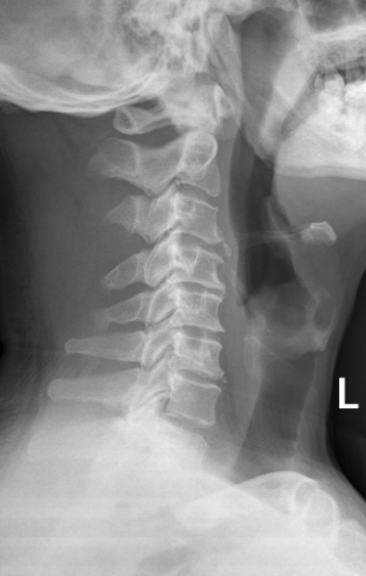

经我院骨病中心脊柱外科医师详细询问病史及查体,并完善相关辅助检查。X线片提示:颈椎生理曲度变直,颈椎骨质增生;CT、MRI提示:颈3/4、颈6/7椎间盘突出,颈4/5椎间盘膨出伴右后突出,右侧椎间孔及椎管狭窄,颈5/6椎间盘膨出伴左后突出,左侧椎间孔及椎管狭窄。综合患者临床症状,最终诊断为混合型颈椎病。

在通过沟通后,骨病中心主任袁毅团队为患者施行显微镜辅助下颈椎前路颈椎间盘切除+椎间植骨融合内固定术(ACDF)。术中在显微镜的辅助下,清楚显露解剖结构,彻底切除椎间盘、骨赘、减压椎间孔,切除后纵韧带,解除脊髓神经压迫,术中出血约20ml。